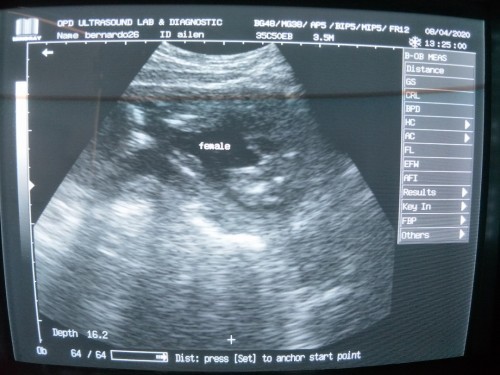

Hello mga momshie just wanna share my experience since last week. Im at 36weeks last week based on LMP. May water leak and nagstart ang pain sa private part and pelvic part. so pinagultrasound ako ng midwife and ng ob ko. and i was surprise na hindi pa tama un size ni baby for her AOG. so bed rest, eat healthy food and drink a lot of water kasi 10.cm nlng un amniotic ko which is boundary na ng normal. At kanina follow up check up ko. same parts ang may pain (mas masakit na maglakad) at na ie ako ng ob ko. matured na daw and ready for delivery na si baby. so need nlng magultrasound to check the amniotic and kamusta na ang baby ko sa loob. and im so happy na okay na ang size nya. (sinunod sunod ko tlga kain last week 😅 para ndi sobrang liit ni baby pag lumabas at syempre pray everyday) and now, we're so ready na lumabas na si baby Thanks God talaga dahil anjan sya lagi to hear and make our prayers possible.🙏❤ #pregnancy #theasianparentph #secondbaby